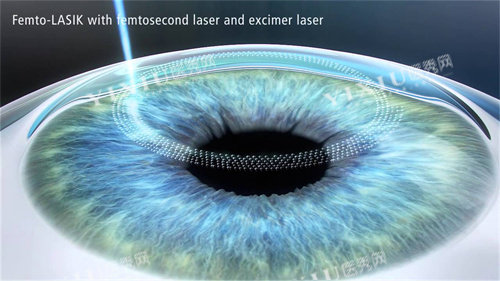

全飞秒手术:小创口技术代表

全飞秒激光手术以切口小、改善比较快著称,2025年价格区间为18000-25000元。例如济南分院报价20000-25000元,而济宁分院通过美团贴补后低至15500元。该术式适合近视度数稳定、角膜条件良好的患者。